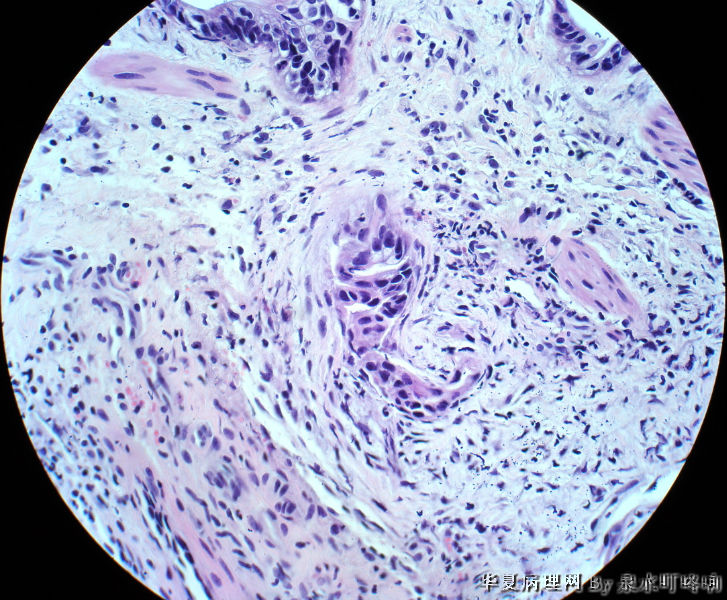

直肠活检

女,49岁,大便变细2年,结肠镜示距肛门5厘米可见溃疡形成,弥漫肠管全周。

腺癌

有黏膜肌层浸润,考虑腺癌。

纤维组织中可见异型腺体浸润,诊断腺癌。